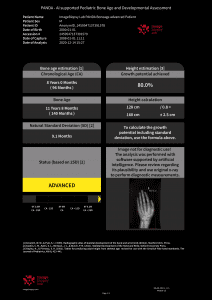

Dr. Richard Ljuhar:IB Lab is aiming to disrupt the way bone and joint diseases are currently being diagnosed. Technologies such as AI-supported software offer a novel way to translate imaging data into structured health information. IB Lab has developed (and certified) a unique MSK-analysis-focused digital workflow platform named IBLAB ZOO. Our deeptech technology is based on state-of-the-art image recognition algorithms and AI, trained on data sets extracted from an accessible image pool of 10 million medical images of various formats. The initial focus of our MSK platform has been on 2D X-ray modules for the knee, hip, hand and spine. The structured information extracted from imaging data enables us not only to disrupt the current workflow by providing standardization and increasing diagnostic accuracy, but also to create new insights into the prediction of disease onset and treatment outcomes.

Dr. Richard Ljuhar: Targeted treatment options ensure shorter periods of suffering, quicker recovery by applying objective assessment/progression measurements and prevention/delay of disease progression, leading to better outcomes. Enhanced and well-structured reports ensure ideal patient communication. MSK diagnoses are often time-consuming and subjective. IB Lab supports radiologists and orthopedists in their daily decision-making with standardized, fast and resource-effective AI-based software solutions for automated measurements on radiographs that accelerate the workflow and improve the time and quality of patient care.